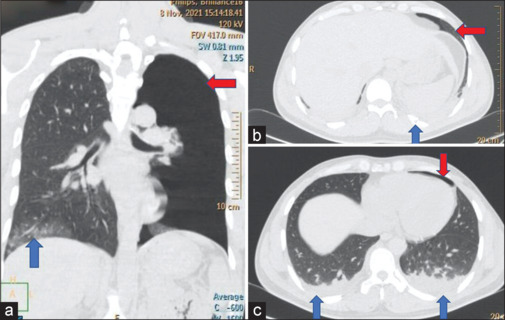

Results: Despatch from greater-than-ideal height (>7 m) and speed (>5 knots) causes a high-velocity impact of the body with water in a non-aerodynamic configuration, exposing maximal body area at penetration. The brunt is borne by the torso/back, specifically, the lungs, ribs, and posterior aspect of the spine. The injuries result from direct trauma, sudden deceleration, barotrauma, and hyperflexion. Computerized tomography (CT) is the imaging of choice in the assessment of these injuries. Prompt evacuation to an equipped center, whilst stabilizing the spine in the suspected, proves pivotal to the outcome.

Conclusions: Adverse slamming dynamics cause accidental injuries in helocasting. Thorax and spine are predominantly traumatized, both directly and indirectly, and are assessed best using CT. Timely spine stabilization and evacuation prove vital. Accurate assessment of height/speed and adherence to their ideal limits, at despatch, may avert such injuries.